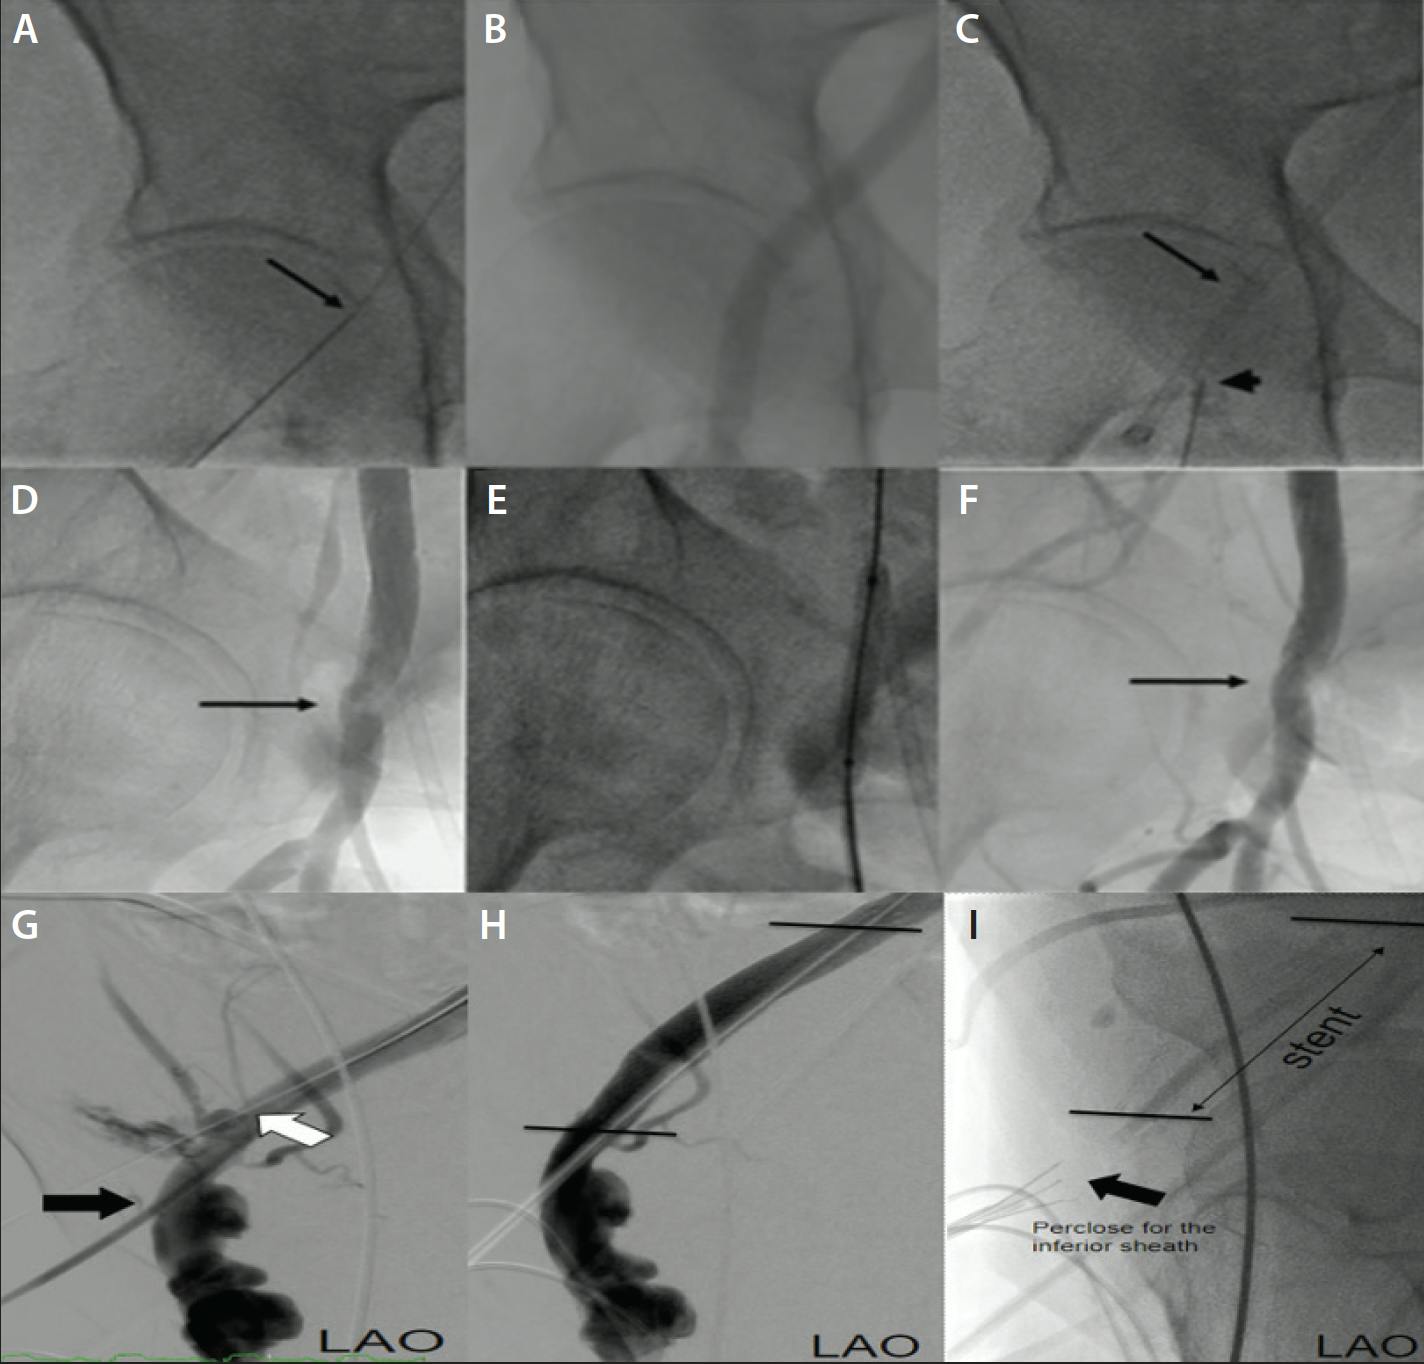

Figure 1. Unilateral arterial access and peripheral complication management during TAVR. Proximal right femoral artery (RFA) access site for TAVR delivery sheath (arrow) (A). RFA angiogram (B). Proximal RFA sheath (arrow) and inferior ipsilateral RFA access site (arrowhead) (C). Completion angiogram via inferior sheath shows delivery sheath site stenosis (arrow) (D). Angioplasty via inferior sheath (E). Resolution of RFA delivery site stenosis (arrow) (F). CFA perforation (white arrow) (G) treated with covered stent placement and balloon postdilation (both via the inferior sheath, black arrow) (H) and preclosure of the inferior access site (I).

We began to use the ipsilateral common femoral artery (CFA) or superficial femoral artery (SFA) inferior to the TAVR site as our secondary access point in 2017 (Table 1 and Figure 1).7 The transition from contralateral to ipsilateral femoral access reflects an evolution in our procedural strategy.7,8 There are numerous potential benefits to this approach:

In rigorously assessing this approach, we found that peripheral vascular complications were similar between patients undergoing TAVR with bilateral access and those with unilateral access (10.8% vs 8.6%; P = .543), demonstrating no increased risk of using the same side.7 In another study by Yan et al,8 single-artery access TAVR achieved similar device success compared with dual-artery access and did not increase the x-ray time or dose. Importantly, no major vascular complication was observed in both groups, and the incidence of minor main vascular and access complications in the single-artery access group was comparable to those of the dual-artery access procedure.